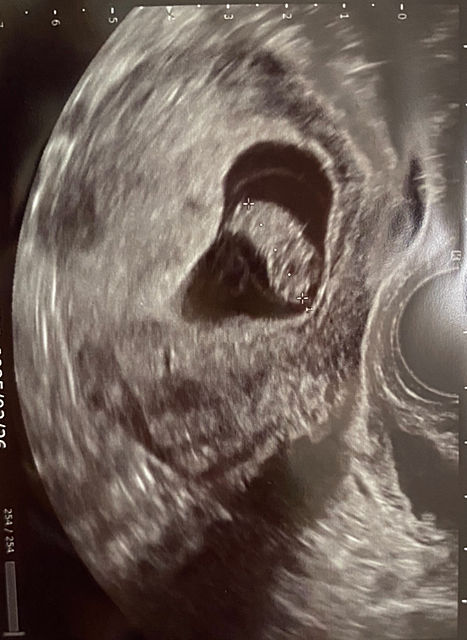

おめ!

暑い日が続くし、しばらくは悪阻も続きます。辛抱しましょう。うちの子はいま約900グラムだとか。この調子で増えていくと3,000グラムは超えそうです。楽しみが待っていると思って大事にしてくださいね。

だいぶ大きくなってきましたね!

うちもしっかり育てたい‥

ちゃんと産んであげたい!

家族を増やしたい